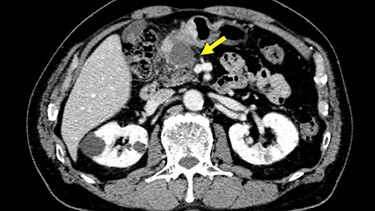

The patient received S-1, oxaliplatin and trastuzumab (SOX+Tmab) (S-1; 120 mg/body/day, days 1–14, oxaliplatin; 130 mg/m2, day 1, trastuzumab; 8 mg/kg for the first week and then 6 mg/kg every week thereafter, day 1). After finishing a total of four cycles of neoadjuvant chemotherapy, the efficacy was evaluated by CT, which showed significant shrinkage of the tumor at the antrum and detachment from the pancreatic head, with no enlarged lymph nodes (Fig. 6). Follow-up EGD revealed a very small ulcerative lesion at the antrum (Fig. 7). The serum level of CEA had decreased to 9.0 ng/ml.

CT after the NAC had been completed showed a significantly shrunken tumor at the antrum that had become detached from the pancreatic head (arrow).